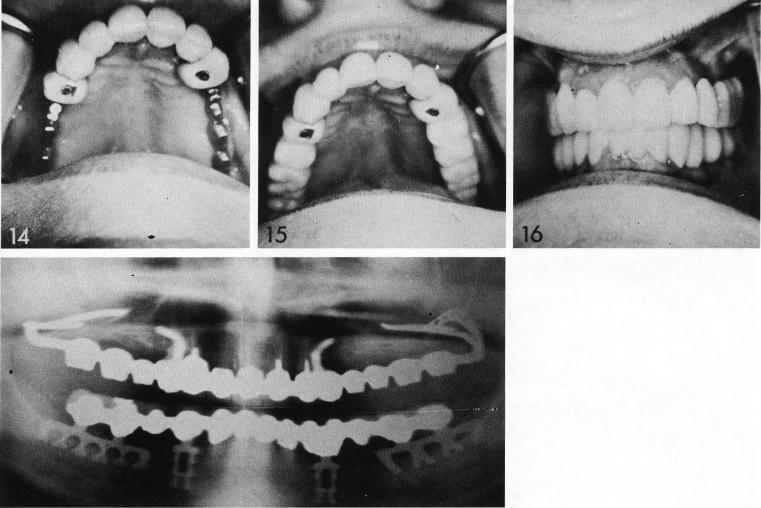

Bilateral pterygoid extension implants were used here. The patient's natural anterior teeth were prepared with internally threaded attachments cantilevered over the edentulous spaces (2) and fitted with Duralay copings (3). The posterior spans were exposed (4), and fitted with prototypes (5,6) picked up in the bilateral impressions (7). The sites were then closed (8). The implants are of the old design (9,10) with a palatal finger (10, arrow) ex-tending from the crown over the internally threaded attachment and the bar arising from the hamular notch. The implants were inserted (11), being screwed into their anterior anchorage (12). The resulting anchorage crowns are bulky (14,15), and for this reason such attachments have been largely abandoned. Also, the tissue usually receded because the anterior palatal strut was a direct extension off the gingival margin of the crown from which it extended—an excellent reason for abandoning the palatal finger.

1 Bulky anchorage maxillary crowns for implants